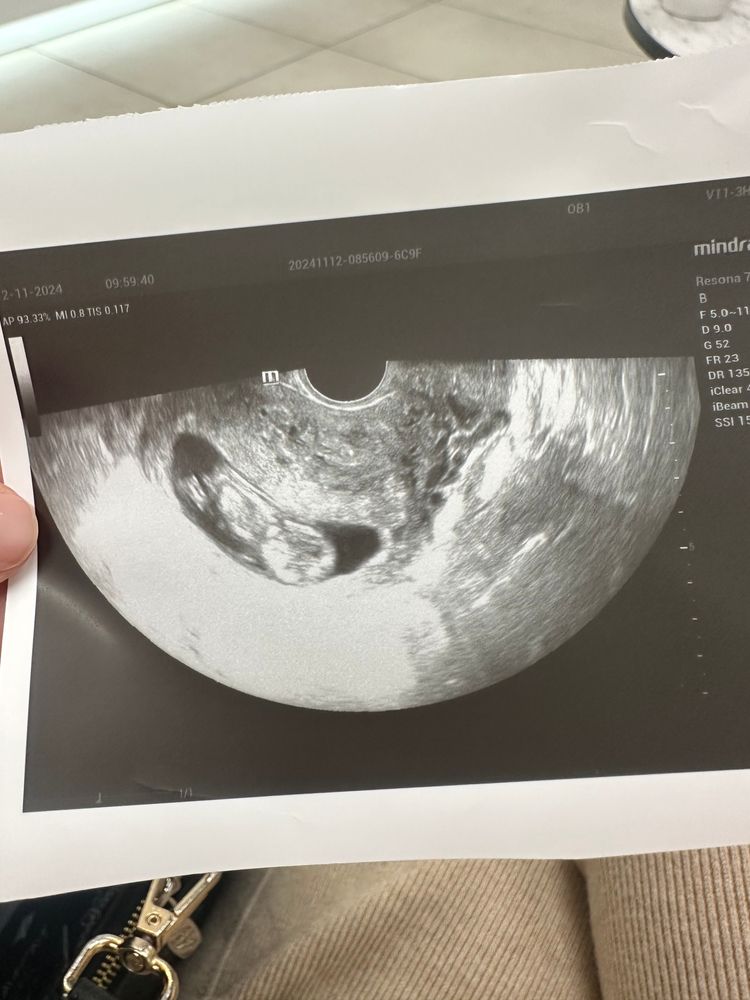

Узи в 11 недель